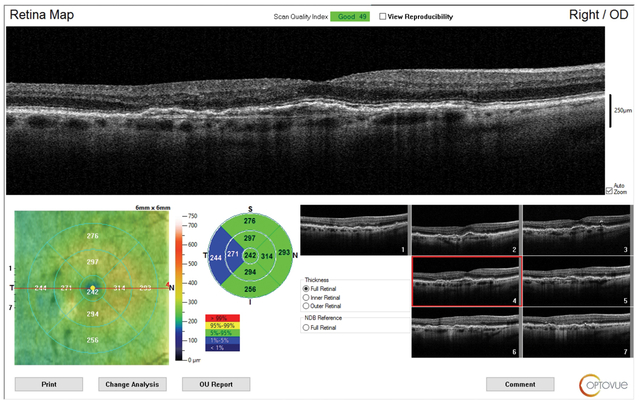

Στη μελέτη συμπεριλήφθηκαν συνολικά 120 παιδιά με μυωπία μεταξύ οκτώ και 13 ετών με διαθέσιμα δεδομένα πάχους χοριοειδούς. Η θεραπεία RLRL πραγματοποιήθηκε χρησιμοποιώντας μια συσκευή επιτραπέζιου φωτός οικιακής χρήσης που εξέπεμπε κόκκινο φως στα 650nm. Το πάχος μετρήθηκε με OCT κατά την έναρξη και παρακολούθηση ενός, τριών, έξι και 12 μηνών.